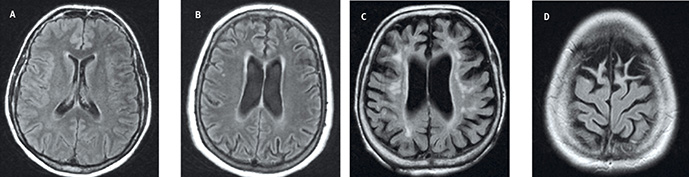

Strukturell hjärnavbildning kan förbättra diagnostiken vid demens

Översikt